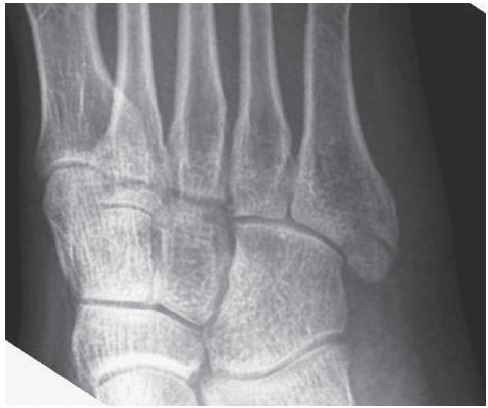

다음은 제5중족골 골절의 네 가지 방사선 영상이다. 손상은 무엇인가?

① 족저근막의 외측열 부착부의 견열 골절

② 단비골건 부착부의 견열 골절

③ 존스 골절(Jones fracture)

제5중족골 감입 골절(impaction fracture)로, 피로 골절으로 종종 시작된다.

④ 손상 부위 없음

이는 제5중족골 기저부의 정상적인 발달성 골돌기(apophysis)에 해당한다.